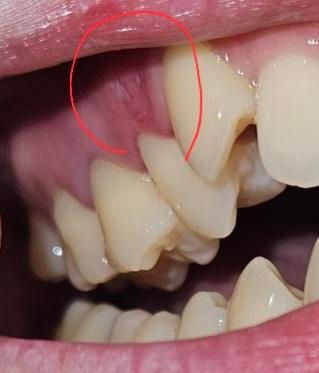

레진한 어금니 윗 잇몸 상처? 파임? 염증? 질문입니다.

5일전 레진한 어금니 윗 잇몸에 상처? 파임? 염증? 뭔진 모르겠는데 양치하고나니 해당 잇몸이 약간 따가움이 있어요. 혀로 문질러보면 울퉁불퉁해요..

• 1번 째 사진

잇몸 사진으로 봐서는 구내염의 양상이고, 며칠 전 치과치료를 받으셨다고하니 해당 부위 잇몸이 자극되거나 피로하여 그럴 수 있습니다. 일주일내로 자연스럽게 완화될 것 같습니다.

레진치료를 할때 잇몸에 자극이 있었다면 구내염등이 생길수 있습니다. 이런 증상은 대부분 2주이내에 없어지게 됩니다.